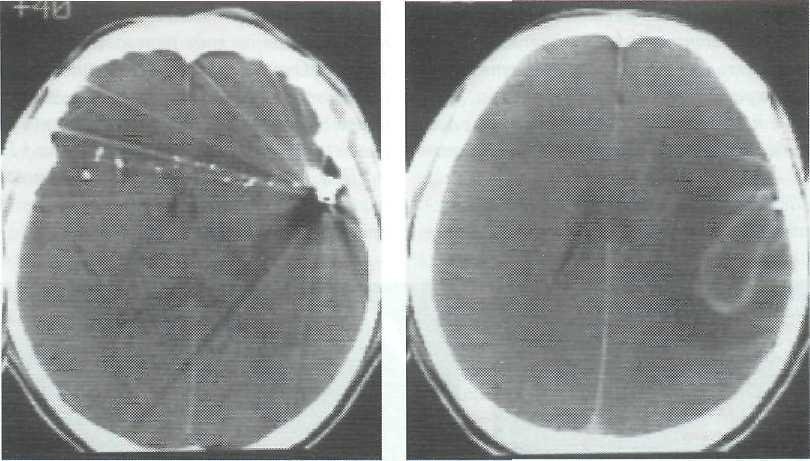

- 1 стадия (1-3 дня) наблюдается энцефалит – это начальное воспаление мозга. Самый легкий период, болезнь поддается излечению благодаря антибактериальной терапии или проходит самостоятельно путем рубцевания.

- 2 стадия (4-9 дней). В абсцессе уже образовался гнойник, который с каждым днем увеличивается в объёмах, если не обращаться к медикам.

- 3 стадия (10-13 дней). Вокруг гнойной полости образуется защитная пленка, которая не дает образованию распространяться дальше.

- 4 стадия (3 неделя). Пленка полноценно уплотнилась. В некоторых случаях начинается регресс болезни или вокруг капсулы образовываются новые очаги заражения.

Дальше это только подготовка к хирургическому вмешательству. Врачи клиник на данный момент практикуют полное удаление абсцесса или его дренирование. Пунктуационная аспирация применяется на ранних стадиях или на этапе церебрита.

Её эффективность доказана в случаях, когда гнойник расположен глубоко в голове. Если неврология больного покажет наличие воздуха в абсцессе или ухудшение общего состояния пациента – новообразование нужно удалять.